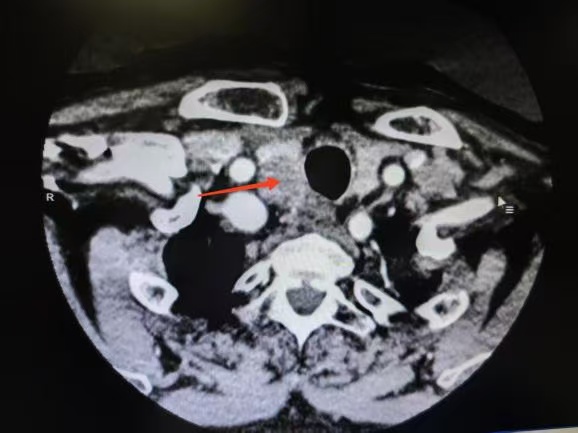

CT箭頭所示:右側(cè)甲狀腺腫瘤

荊楚網(wǎng)(湖北日報(bào)網(wǎng))訊(通訊員 楊青青 沈浩元 )近日,孝感市中心醫(yī)院甲狀腺乳腺外科成功為一名67歲男性患者實(shí)施了高難度甲狀腺癌根治手術(shù)。該患者因頸部突發(fā)硬塊4天就診,經(jīng)檢查確診為雙側(cè)甲狀腺乳頭狀癌伴右頸側(cè)區(qū)多發(fā)淋巴結(jié)轉(zhuǎn)移,術(shù)中進(jìn)一步發(fā)現(xiàn)腫瘤已侵犯包繞喉返神經(jīng),側(cè)區(qū)轉(zhuǎn)移淋巴結(jié)亦侵犯頸內(nèi)靜脈,病情復(fù)雜且兇險(xiǎn)。